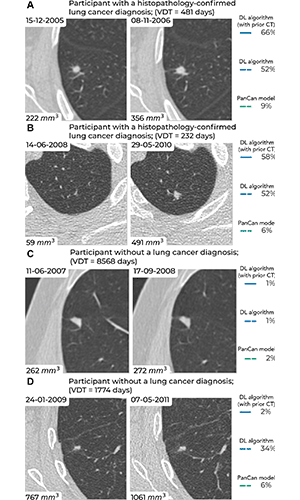

Examples of screening-detected pulmonary nodules from the Danish Lung Cancer Screening Trial (DLCST) and the Multicentric Italian Lung Detection Trial (MILD), wherein malignancy risks were estimated accurately by the deep learning (DL) algorithm that combines a current and prior CT examination. The lines correspond to the malignancy risk estimation algorithms (solid blue, DL algorithm with prior CT; dotted blue, DL algorithm; dotted green, PanCan model). The percentages correspond to the risk scores from 0% to 100%. (A) Annual low-dose axial chest CT images in a 55-year-old woman with a lung cancer diagnosis in the DLCST show a growing spiculated malignant nodule, with a volume doubling time (VDT) of 481 days. All algorithms produced high malignancy risk scores. (B) Biennial low-dose axial chest CT images in a 67-year-old man with a lung cancer diagnosis in the MILD show a growing malignant nodule (VDT, 232 days). The DL algorithms produced high malignancy risk scores. (C) Annual low-dose axial chest CT images in a 66-year-old male participant without a lung cancer diagnosis in the DLCST show a stable benign nodule in which all algorithms produced low malignancy risk scores. (D) Biennial low-dose axial chest CT images in a 78-year-old male participant without a lung cancer diagnosis in the MILD show a stable part-solid benign nodule, in which the DL algorithm, which combines current and prior CT, produced a low malignancy risk score. However, the algorithm that only processed a single CT produced a high malignancy risk score. PanCan = Pan-Canadian Early Lung Cancer Detection Study. https://doi.org/10.1148/radiol.223308 ©RSNA 2023